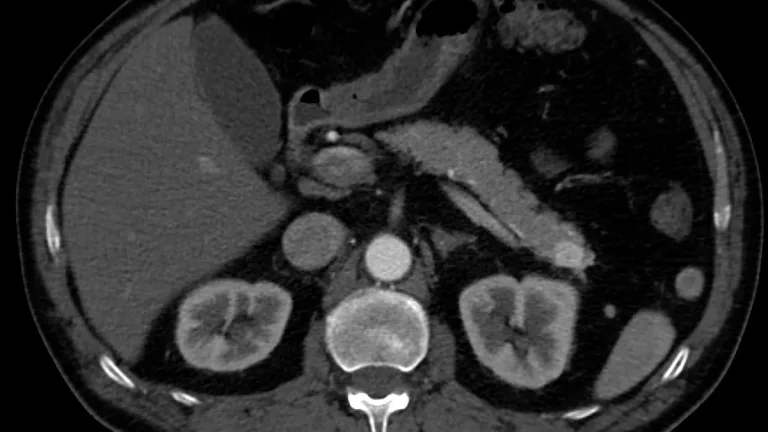

Cáncer de páncreas

Getty Images/ Foto referencial

Globalmente, noviembre es el mes de concientización para este cáncer, cuya tasa de supervivencia es una de las más bajas. Más del 80% de los casos se diagnostican en etapas avanzadas.

La participación de Oncomeds en protocolos internacionales acerca a pacientes chilenos a terapias moleculares e inmunoterapias experimentales, la única vía para revertir su curso.